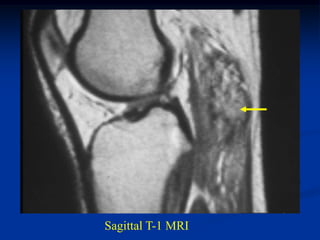

Case #295.1           Recurrent hemangioma

24 year female with recurrent hemangioma triceps

Coronal T-1   T-2

Sagittal T-1   T-2

Case #295.1 Recurrent hemangioma phleboliths 24 year female with recurrent hemangioma triceps